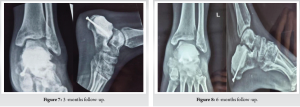

Postoperatively, the patient was kept non-weight bearing for 6 weeks, followed by partial weight bearing up to 3 months, and allowed full weight bearing then onward. The patient was followed up at 3 months (Fig. 7), 6 months (Fig. 8), and 1 year (Fig. 9) for any evidence of recurrence or articular collapse.